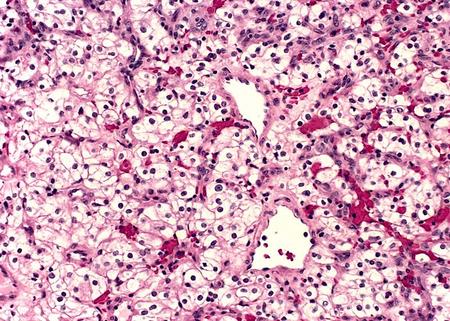

El carcinoma corticosuprarrenal secretor puro de aldosterona (APAC puro) es una forma muy rara de (hiper) aldosteronismo primario (AP; consulte este término) que puede corregirse quirúrgicamente, y que es debida a una neoplasia suprarrenal secretora de aldosterona.

El APAC puro se caracteriza por: supresión de renina, hipersecreción unilateral de aldosterona e hipertensión de moderada a grave que puede estar asociada a una hipopotasemia, y la presencia de un tumor suprarrenal grande. La hipopotasemia puede ser sintomática y presentarse como debilidad muscular, calambres, parestesias o palpitaciones con o sin fibrilación auricular.

El diagnóstico del carcinoma se sugiere a través de un TAC, mostrando un tumor que excede los 4 cm de diámetro, y la posible metástasis y/o invasión de la vena cava inferior. Una laparotomía abierta permite la reseccción del tumor y de las posibles metástasis de los órganos adyacentes.